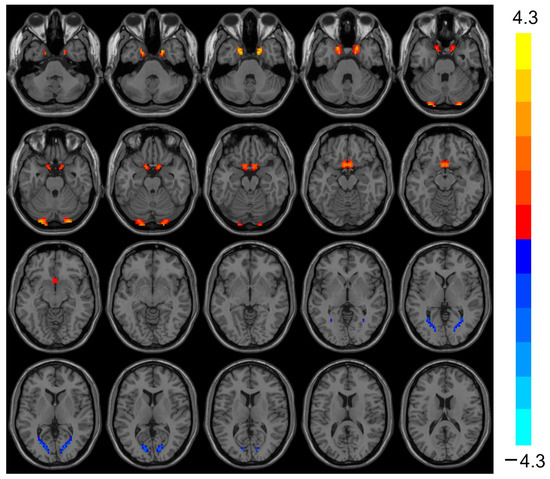

VMHC was elevated (t = 3.803, p < 0.001) in the bilateral Cerebellum_Crus1 of the heart transplant group, while VMHC was reduced (t = −3.424, p < 0.001) in the bilateral calcarine, as shown in Table 3 and Figure 2.

Figure 2.

VMHC values were elevated in the heart transplantation group in bilateral Cerebelum_Crus1 (red), whereas they were reduced in bilateral calcarine (blue). Color bars are t-values. VMHC, voxel-mirrored homotopic connectivity.

VMHC is a validated rs-fMRI evaluation method for quantifying the functional connectivity between the two cerebral hemispheres and is one of the most prominent features of the brain’s basic functional architecture. In pathological states, altered communication between the two cerebral hemispheres can significantly impact cognition and behavior [28]. In this study, VMHC was elevated in the bilateral Cerebellum_Crus1 and decreased in the bilateral calcarine in the heart transplant group. Decreased VMHC in the bilateral calcarine, a primary visual cortex, may indicate disrupted visual information processing, potentially explaining visuospatial deficits in patients. An increasing number of studies recognize that the cerebellum is not only involved in maintaining body balance, motor coordination, and eye movements [29] but also plays a significant role in sensory, cognitive, and emotional learning and regulation [30]. Elevated VMHC in the Cerebellum_Crus1 might indicate maladaptive plasticity in chronic cognitive impairment. Many studies have used fMRI to map motor and non-motor task processes and resting-state networks in the human cerebellar cortex [31]. Pagen et al. found that the functional connectivity of the cerebellum to the brain’s default mode network (DMN) was generally reduced in patients with amnestic mild cognitive impairment (MCI) [32]. The DMN is primarily responsible for the body’s cognitive control in the resting state and maintains inward thinking activity. In patients with Alzheimer’s disease, the DMN is initially disrupted by amyloid deposition caused by the disease process [33]. Both the cerebellum and the prefrontal lobe belong to the DMN. The reduced ReHo in the prefrontal lobe and elevated VMHC in the cerebellum in this study suggest that the DMN is damaged in heart transplant patients.